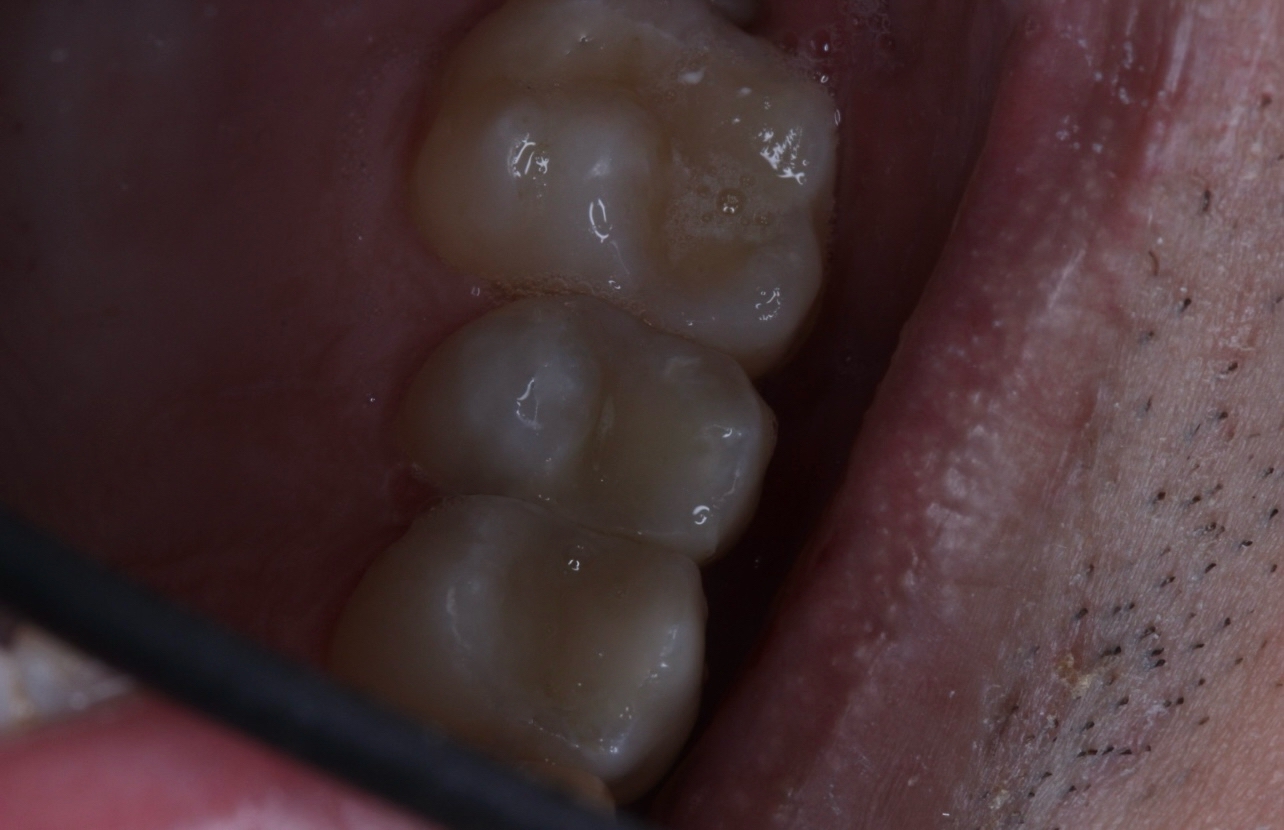

1000070961.jpg 180Кб, 882x704

882x704

Зуб пятерка. Возможно такое вылечить, анонче? Отклолся как то, вообще не болит.